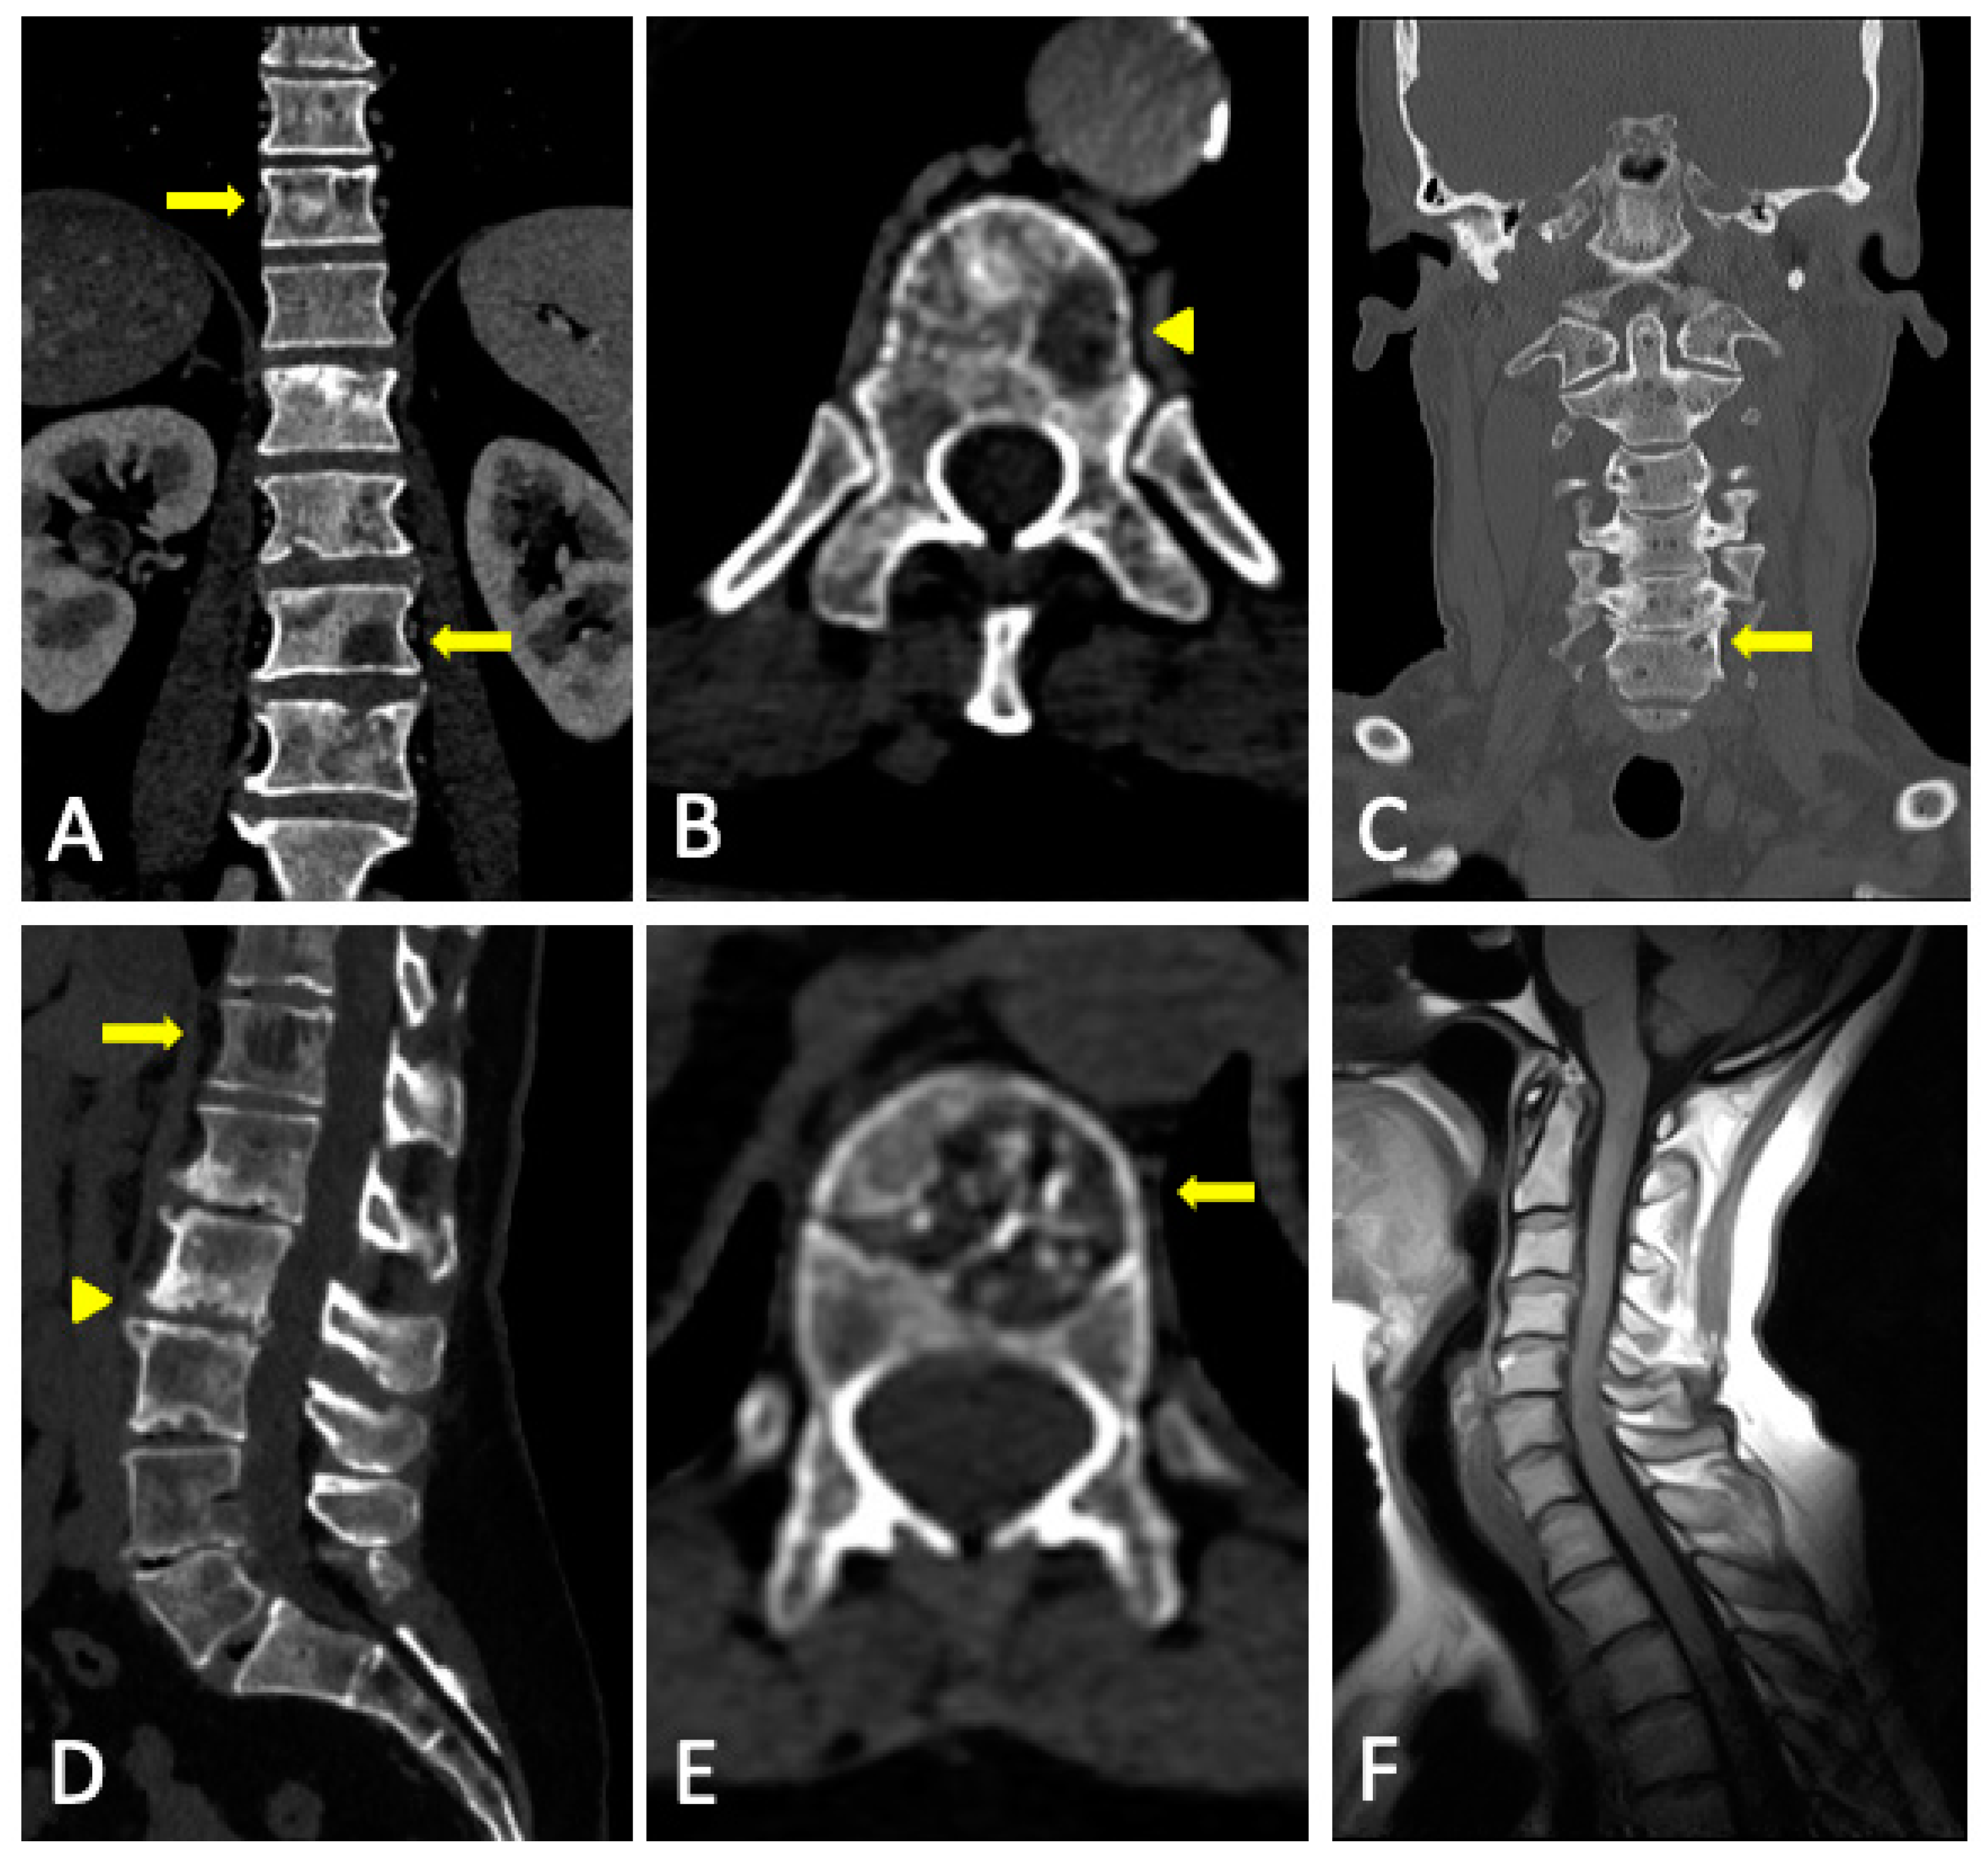

3.2. Imaging Findings

3.3. Role of DECT

3.4. DECT vs. Conventional CT